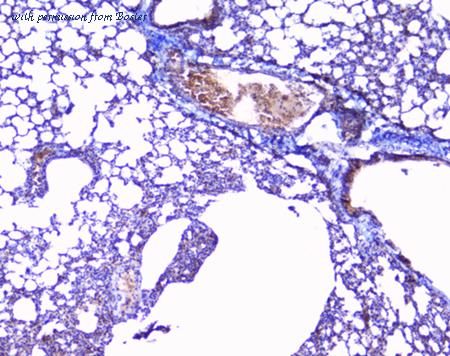

gene information - mouse Col3a1

- synonym:AW550625; Col3a-1; Tsk-2; Tsk2; collagen alpha-1(III) chain; procollagen, type III, alpha 1

- description:collagen, type III, alpha 1